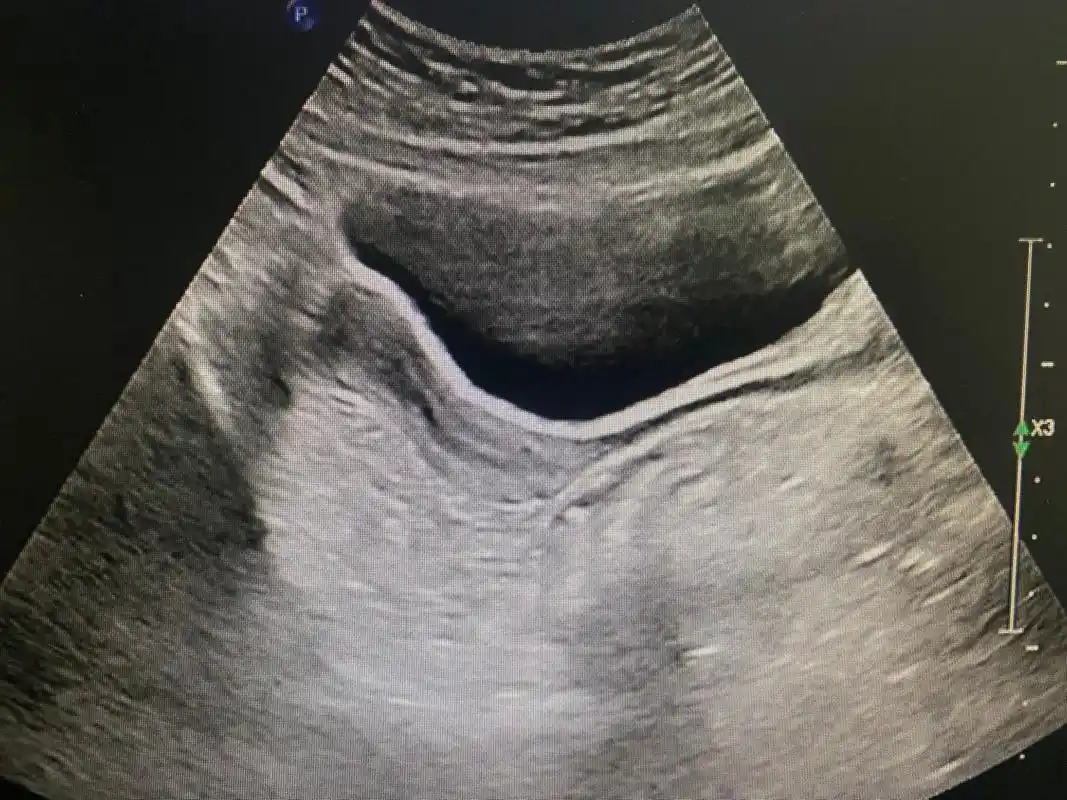

幼稚子宫 - 超声医学讨论版 - 爱爱医医学论坛

正常早期妊娠子宫超声所见(一)